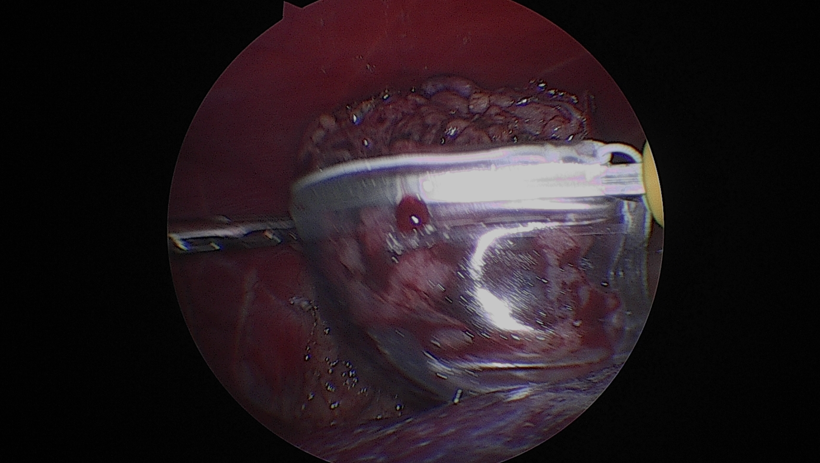

수술 과정은 다음과 같이 진행되었습니다.먼저종양이 위치한 신장을 후복막에서주변 조직과 분리하였습니다.

신장을 충분히 노출한 뒤, 신혈관을 순차적으로 처리했습니다.우선신정맥을 둔성으로박리하여 분리한 뒤, 클립으로 결찰하고절단하였습니다.

이어서 신동맥역시 같은 방법으로 둔성박리 후 클립 결찰후 절단하였습니다.

그 다음 신장에서 이어지는 요관을 따라 원위부로 추적하여 방광에 가까운 지점에서 둔성분리한 후 클립으로 결찰하고절단하였습니다.

이렇게 신장, 혈관, 요관이 모두 안전하게 분리된 것을 확인한 뒤, 적출된 신장을 수거 백에넣어 복강 내 오염 없이 외부로 제거하였습니다.

최소침습적 접근을 통해 조직 손상을 줄이고 통증을 최소화하면서, 종양을 안전하게 제거하는 데 중점을 두고 수술을 진행하였습니다.

환자는 고령이었기 때문에 수술 후 통증과 회복 부담을 최소화하고자 복강경을 이용한 최소침습적 신장적출술을시행하였습니다.수술 과정은 다음과 같이 진행되었습니다.먼저종양이 위치한 신장을 후복막에서주변 조직과 분리하였습니다.